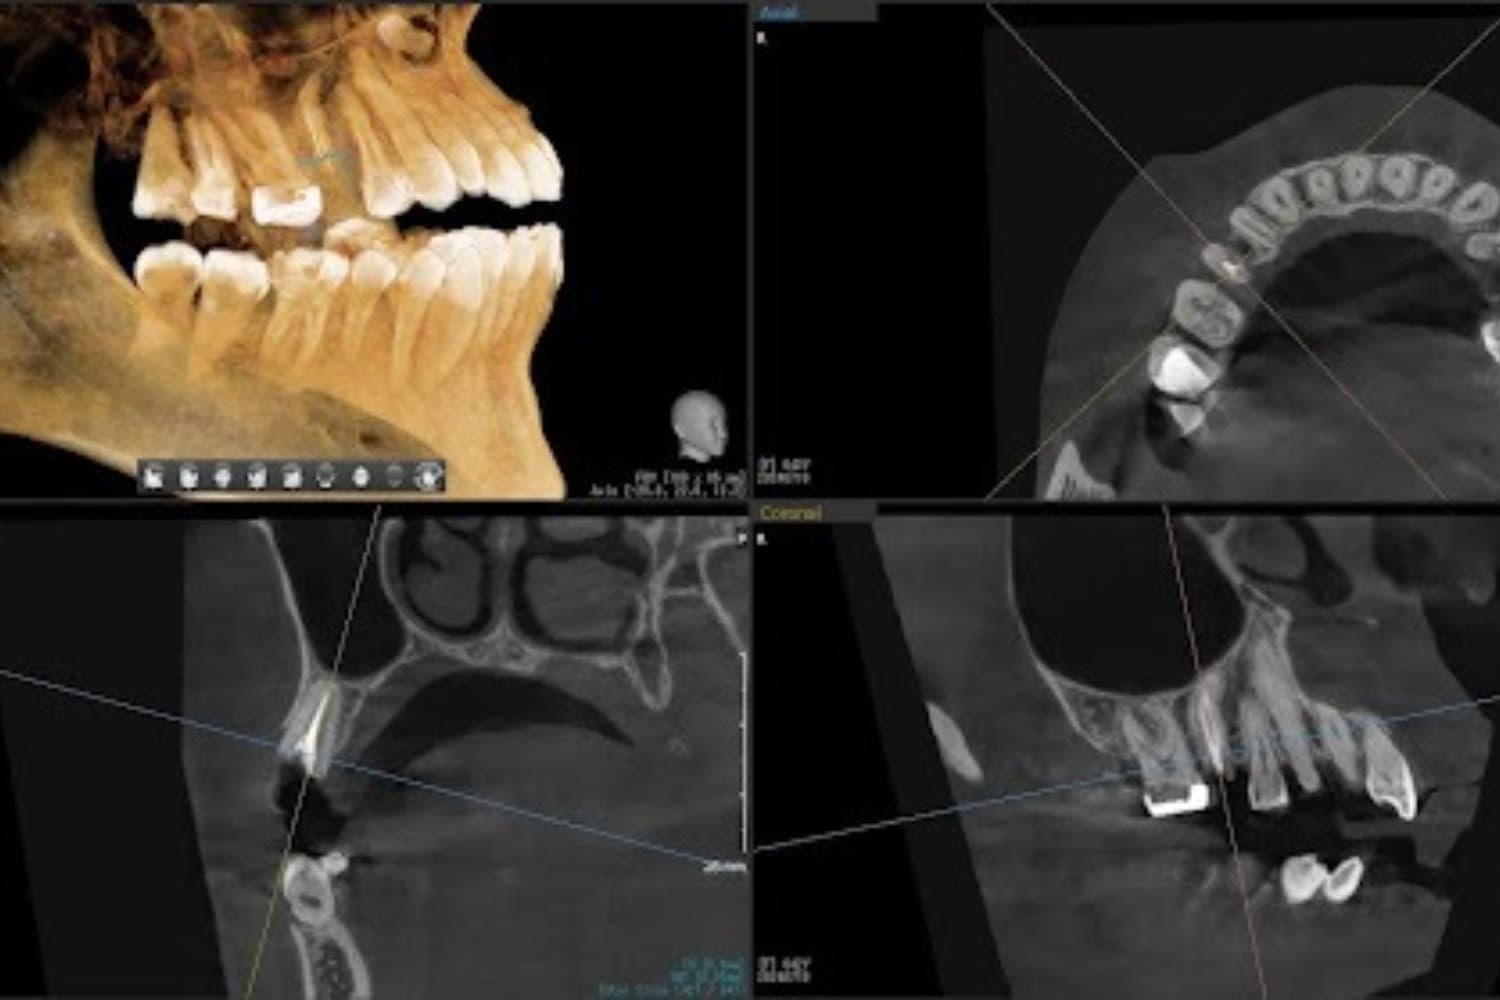

左上の歯のインプラント治療(60代女性)

Before

インプラント抜歯即時埋入・即時荷重(抜歯と同時にインプラントを埋入し、当日に仮歯を入れる)

年齢

60代

性別

女性

主訴

重度の歯の動揺があり、何もしていなくとも痛みがある。治療にあたって前歯がないことを気にする。

治療期間

4ヵ月

治療回数

10回

費用

814,000円(税込) 費用の内訳: 【インプラント基本料】330000円×2=660000円(税込み) 基本料金に以下を含む ・フィックスチャー及び手術費用 ・投薬費用、 ・レントゲン費用 ・インプラント上部費用(アバットメントおよびジルコニアクラウンの費用用) 【オプション費用】 ・右上5グラフトレスサイナスリフト費用 33000円(税込み) ・右上3抜歯即時荷重費用 33000円(税込み) ・暫間インプラント費用 0円

副作用・リスク

・手術後に痛み・腫れ・出血・合併症等を引き起こす恐れがあります。 ・噛む感覚がご自身の歯と異なることがあります。 ・見た目がご自身の歯と異なる場合があります。 ・手術後もメインテナンスを続けないと、インプラントが抜け落ちてしまう恐れがあります。